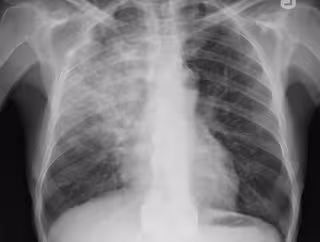

Investigadores estadounidenses comprueban que unas células pulmonares ayudan a p

Investigadores estadounidenses comprueban que unas células pulmonares ayudan a p - FLICKR/YALE ROSEN - Archivo

Investigadores de la Universidad de Boston (Estados Unidos) han comprobado que las células inmunes llamadas TRM, que se encuentran en los pulmones, son capaces de protegerlos frente a infecciones bacterianas como, por ejemplo, las que causan la neumonía.

Asimismo, utilizando modelos experimentales, los expertos, cuyo trabajo ha sido publicado en la revista 'Mucosal Immunology', han observado que la recuperación de la neumonía bacteriana cambia el tejido pulmonar previamente infectado.